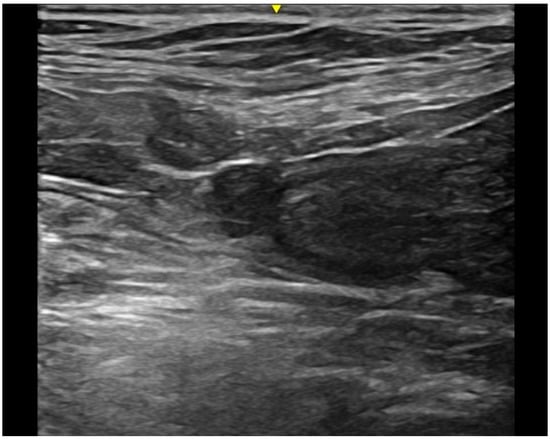

Intramural vesicourachal diverticulum was the most prevalent UA diagnosed in both cats (76.7%), and dogs (71.1%). These varied in size, from thin anechogenic lines perpendicular to the wall, in the ventro-cranial portion of the bladder, to formations of greater width, up to 0.4–0.5 cm. Its content was variable, from anechoic to slightly corpuscular, in relation to the bladder corpuscularity (Figure 2).

Figure 2. Longitudinal ultrasound image of the urinary bladder in a dog, showing the presence of a small (<1 cm diameter), well-defined, fluid-filled, anechoic structure in the cranioventral bladder wall, consistent with intramural vesicourachal diverticulum.